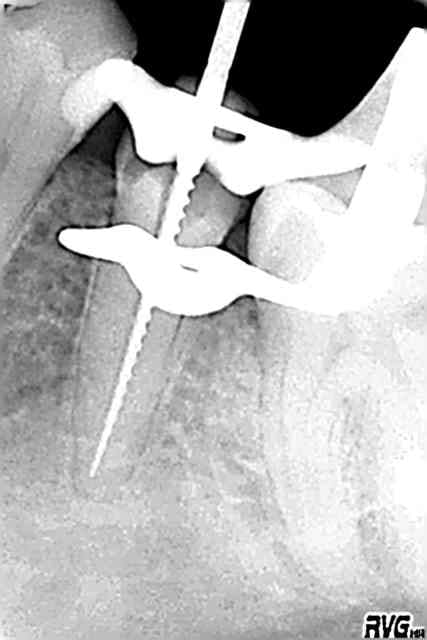

D'apres mon confrere le Dr. Vafancullo; si tu ouvres correctement ta cavité, degages 2 ou 3 mm a la fraise de touati autour de ton protaper, il se pourrait meme que les US à fond les manettes suffisent .

Parce qu'une fois bien accessible dans l'axe; il est qd meme peté tellement haut qu'on croirait un screw-post

oui ben parfois, t'y arrives, parfois, tu casses encore plus le protaper (ou autre)et une partie s'enfonce un peu plus....

Aprés, on fait ce qu'on peut sur une 48 ou deux instruments ont été découverts fortuitement...ou presque

ça a pas du te prendre 5 minutes!!!

US et fraise, c'est vraiment pour le cas de depart cassé extremement haut